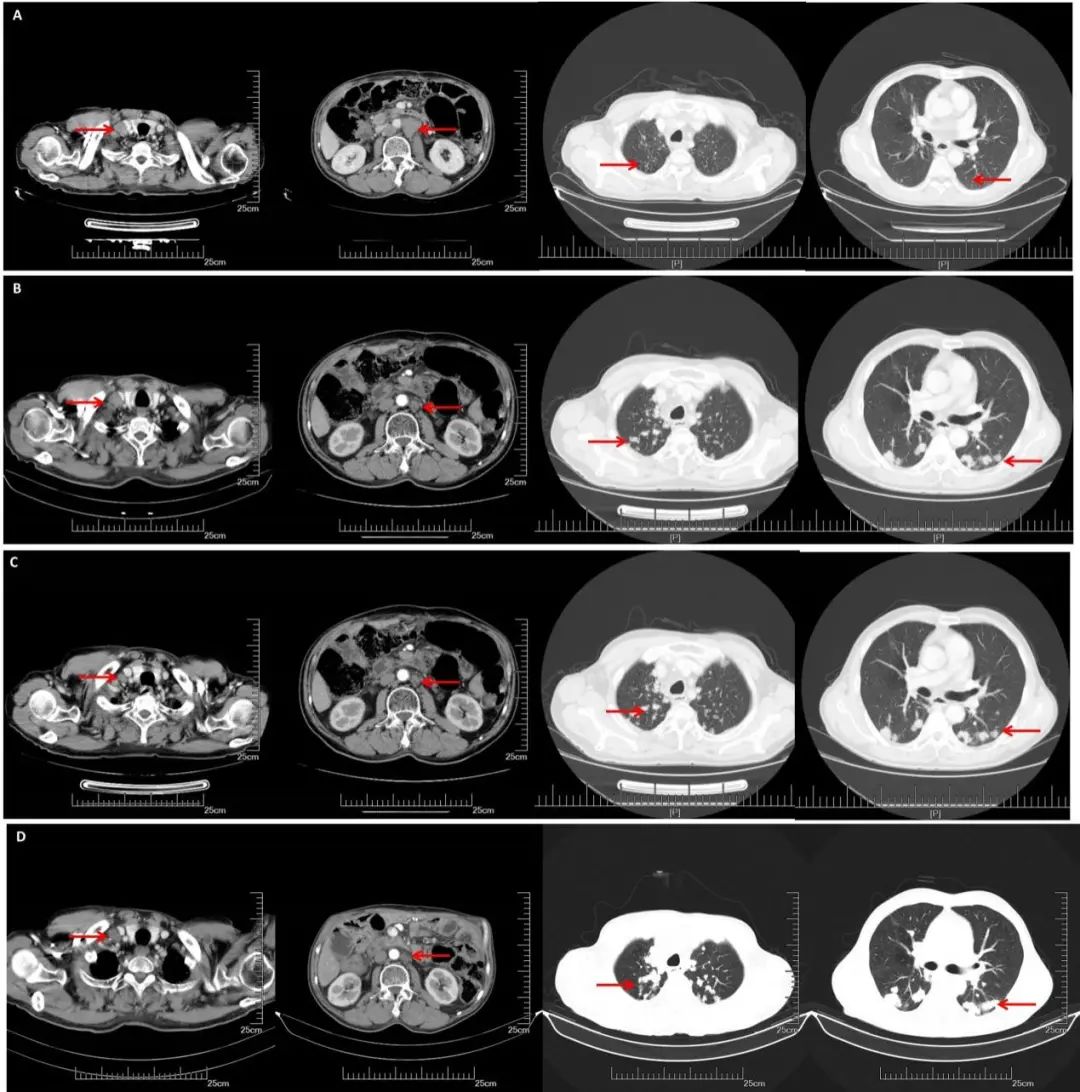

CT(2019. 5.16):双侧锁骨上、双侧膈肌脚后间隙、脊柱左旁及纵隔多发淋巴结,部分较前增大:腹膜后及右侧髂血管旁多发淋巴结,部分较前减小。余较前相仿。双肺多发转移瘤。较前增多增大。

CT(2019.10.25):双肺多发转移结节,较前明显增多增大。双侧锁骨上、双侧膈肌脚后间隙、脊柱左旁、纵隔多发肿大淋巴结,较前变化不明显。

2019.10.26、2019.11.27、2019.12.25、2020.01.19、2020.2.29采用“曲妥珠单抗+安罗替尼+卡培他滨”治疗5个周期(曲妥珠单抗 8mg/kg,卡培他滨 1.5 d1-14,安罗替尼 10mg q21)。

CT(2020.05.27):双肺多发转移瘤,较前大致相仿。双侧锁骨上、双侧膈肌脚后间隙、脊柱左旁、纵隔、腹腔、腹膜后及右侧髂血管旁等多发淋巴结,部分肿大,较前大致相仿。

疗效评价:SD

A:CT增强(2018.11.07): 腹膜后多发淋巴结转移,部分较前增大。双侧锁骨上淋巴结转移,部分较前增大,双肺多发结节,转移可能;B:CT增强(2019.05.16):腹膜后淋巴结较前缩小,双肺转移较前增多增大;C:CT增强(2019.10.25):腹膜后淋巴结稳定,双肺转移较前增多增大;D:CT增强(2020.05.27):双肺转移瘤及腹腔淋巴结总体稳定。